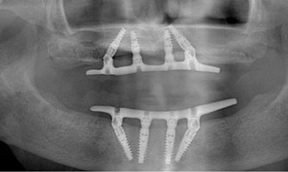

The Toronto Conference in 1982, chaired by Professor George Zarb and presented by Professor Per-Ingvar Brånemark, was a seminal event that changed edentulous treatment planning concepts irrevocably. No longer was it necessary to rebuild lost bone through grafting alone in either arch. The severely atrophic mandible, for example, could be treated with as few as four implants used to support a bone-sparing prosthesis through integrated tooth analogs, as demonstrated in Figure 1 through Figure 3. Here, an 81-year-old patient presented with severe mandibular atrophy (Figure 1) from denture wear since a very young age and had a history of being unable to manage a mandibular prosthesis despite numerous attempts at new denture construction. Four vertical machined-surface osseointegrated implants were placed in 1983 by Professor Brånemark, and all four penetrated the inferior cortex up to 3 mm to 4 mm in depth, as shown on the immediate postoperative panoramic film (Figure 2). At 4 years and 5 months, reparative bone had formed to the apices of all implants (Figure 3), and all of them remained in uncompromised function until the patient passed away at age 90.

Fig 2. Four vertical machined-surface osseointegrated implants placed in 1983 penetrated the inferior cortex up to 3 mm to 4 mm in depth, immediate postoperative.

Figure 2

Fig 3. At 4 years and 5 months follow-up, reparative bone had formed to the apices of all implants.

Figure 3